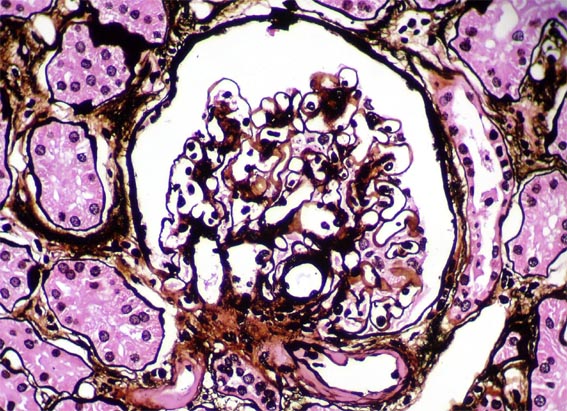

Figura 7.

Plata-metenamina, X400.